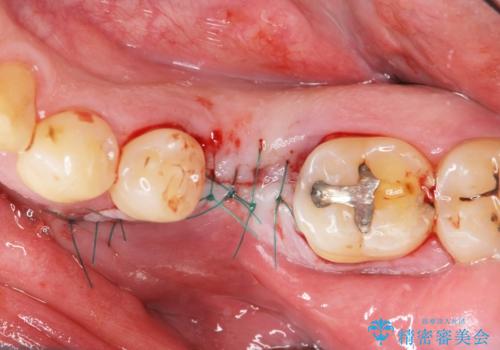

- 奥歯を失ったのち放置してしまった部位にインプラント治療を希望されて来院されました。

少量の骨造成を併用したインプラント治療を計画します。

- 外科手術のため、術後に痛みや腫れ、違和感を伴います